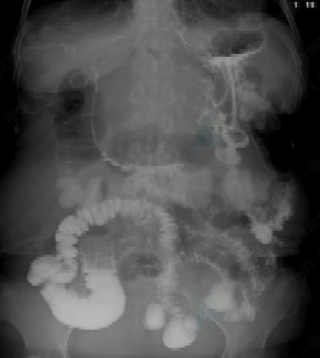

术前胃肠道泛影葡胺造影胃流出道梗阻,造影剂通过不良

经过细致周密的术前准备,在与患者及家属充分沟通并获得理解与同意后,手术如期在交大一附院消化内科介入室开展。手术过程中,在超声内镜实时监测与 X 线透视的双重精准引导下,双蘑菇头全覆膜支架成功被桥接于胃与空肠上段,快速且高效地为患者搭建起新的营养通道。此次手术在第二军医大学消化内科王凯旋教授的专业指导下,由我院消化内科张娟教授及超声内镜团队共同协作完成。从超声内镜探查、X 线定位,到穿刺操作、支架释放,再到营养通道成功建立,整个手术流程衔接顺畅、一气呵成,全程仅耗时 30 分钟。术后第二天,患者便可开始进食流食,造影检查显示支架通畅,肠道显影充分,造影剂通过顺利;术后 3 天,患者已能正常摄入普食。术后 1 周,患者的各项营养指标(如白蛋白、血红蛋白)均稳步上升,顺利达到出院标准。